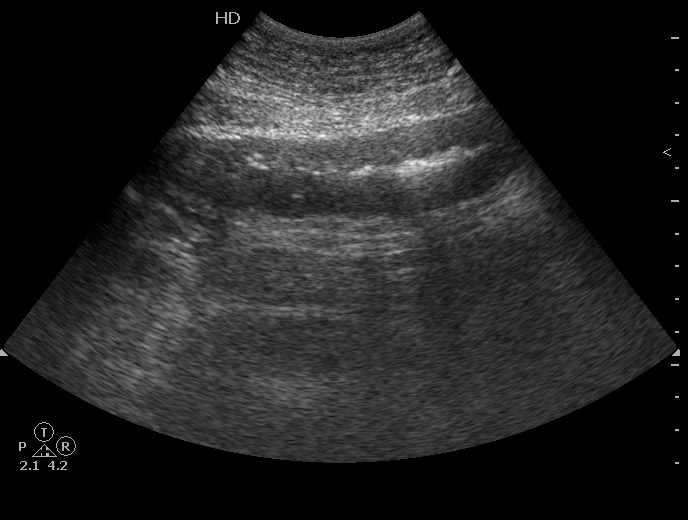

Молодая женщина, 36 лет.

Три дня назад поступила с жалобами на боли в животе в эпигастральной области. При УЗИ в БП небольшое количество жидкости - в малом тазу.

Аппендицит клинически исключен.

Повторный осмотр в связи с усилением болей в животе, появлением инфильтрата в эпигастральной области, снижением гемоглобина.

При УЗИ патологии печени, ЖП, панкреас, селезенки, почек не выявлено, имеется примерно прежнее количество свободной жидкости плюс изменения тонкой кишки:

При операции выявлен сегментарный тромбоз вен брыжейки тонкой кишки с некрозом петель.